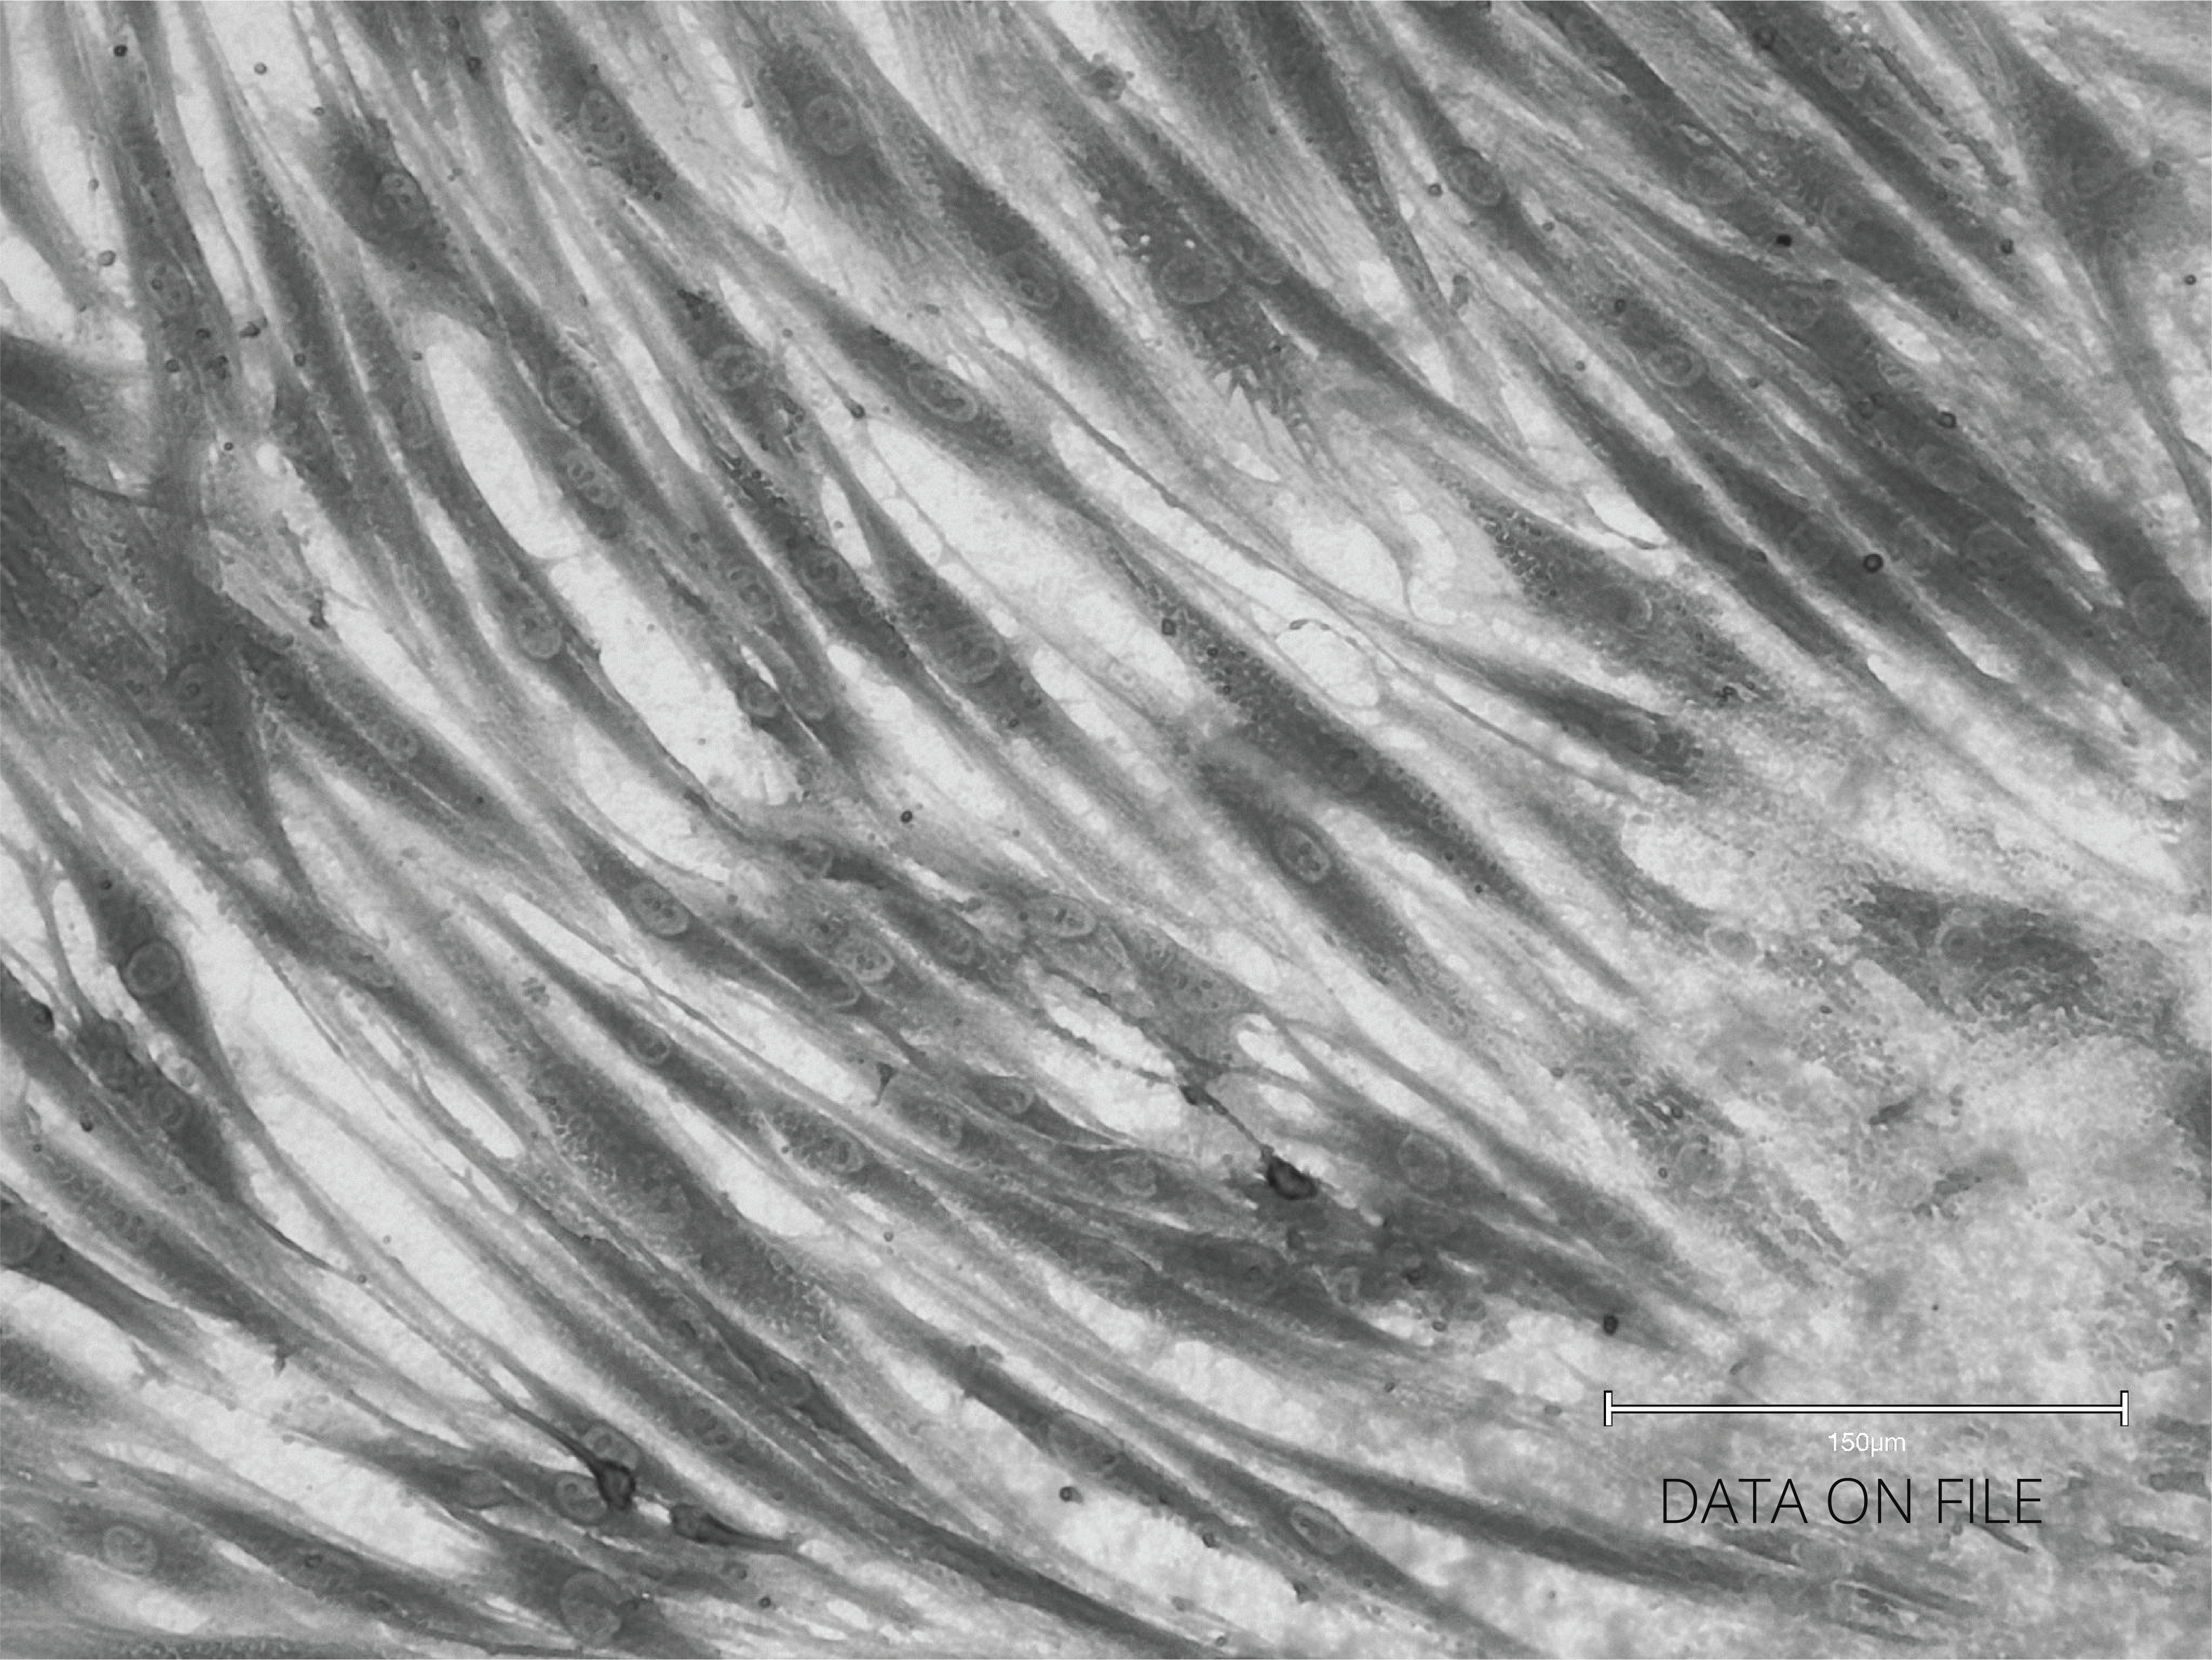

Healthy Fibroblast After RLX-201

RLX-201 Treated

Cultured fibroblast from abdominal skin treated with RLX-201; fibroblast cells were observed to be more elongated post treatment, metabolically active, and healthier